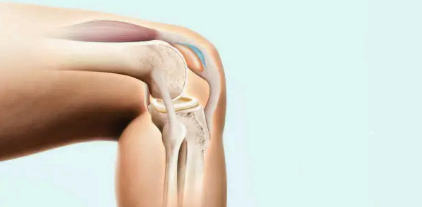

위에 사진 중 노란색으로 되어있는 연골과 연골 사이의 매트릭스 구조의 역할을 하는 연골 탄성섬유의 주성분이 콘드로이친으로 관절 윤활제로써 연골의 마모를 감소시키며 연골 세포 생존에 필요한 영양공급을 성분입니다.